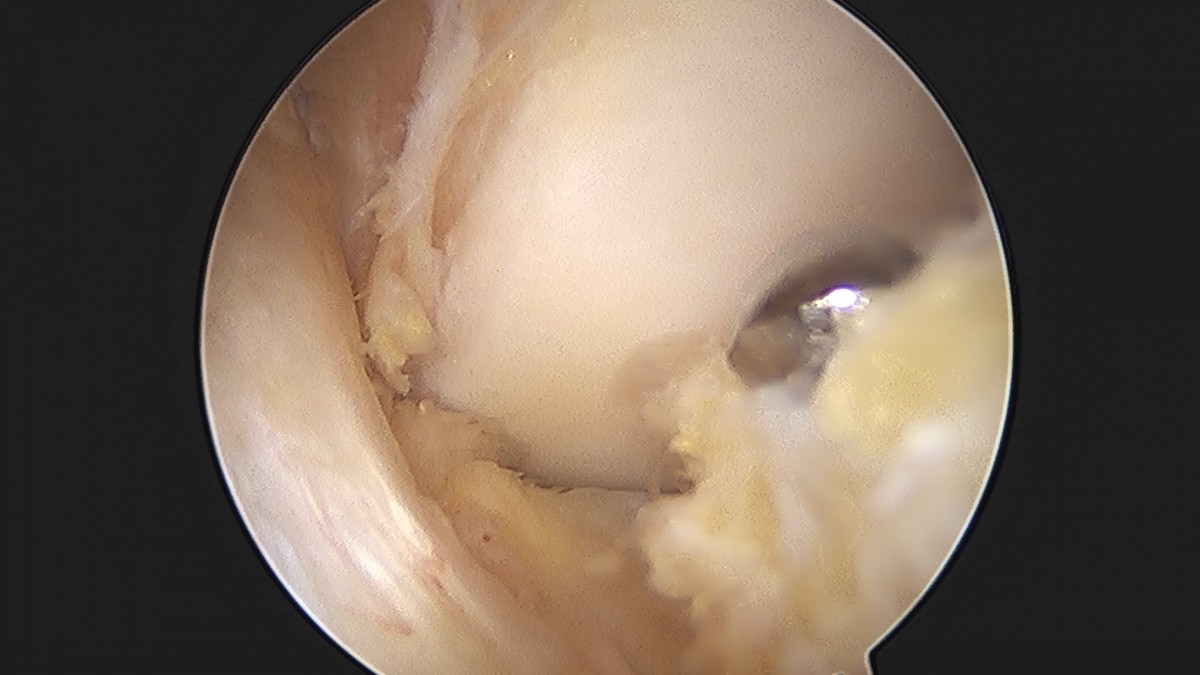

이재상원장님 무릎 반월상 연골판 절제술 김민O 환자

작성자 최고관리자 댓글 0건 조회 365회 작성일 25-09-16 16:10